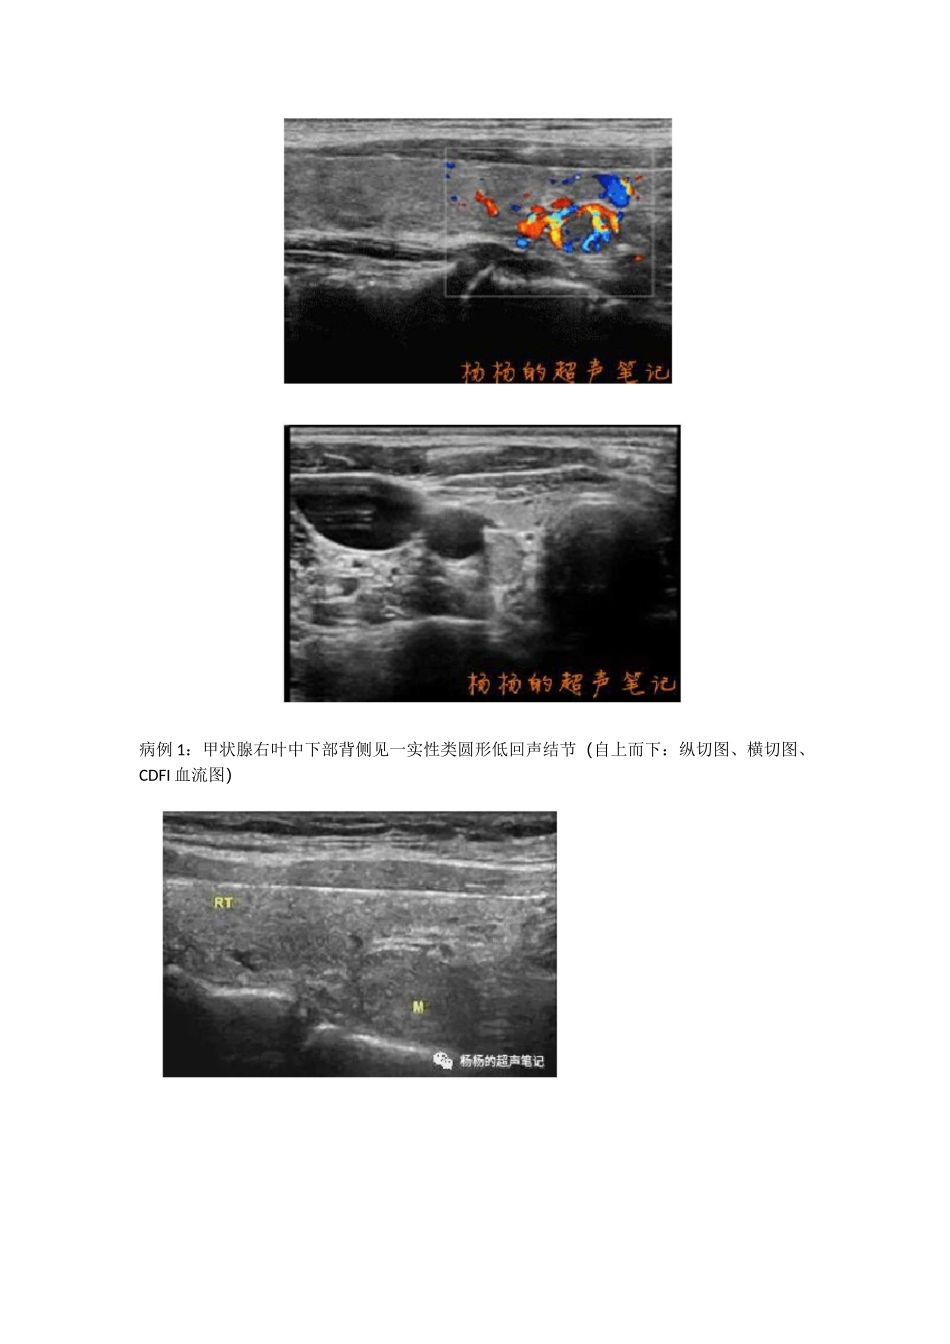

極艳締履尹笔池是甲状旁腺病变呢?如下我们在做甲状腺超声检查时有时会在甲状腺背侧区看到低回声结节,这是甲状腺结节呢?16ZT 结节性甲状腺肿一容易误诊的甲状腺肿甲状腺结节是甲状腺里面的包块,多数为良性甲状腺腺叶后外侧缘的结节状突出部分,它是胚胎早期后鳃体和甲状腺中部融合而形成,一般右侧多见,是甲状腺手术中识别喉返神经及其分支与上甲状旁腺的重要标志,受到甲状腺外科医师的重视f病例 1:甲状腺右叶中下部背侧见一实性类圆形低回声结节(自上而下:纵切图、横切图、CDFI 血流图)病例 2:甲状腺右叶中下部背侧见一实性椭圆形低回声结节(自上而下:纵切图、横切图、CDFI 血流图)f 上图两例患者因甲状腺恶性结节做了甲状腺全切手术,术后病理提示甲状腺右叶结节均为结节性甲状腺肿,不过这类结节却容易误以为是甲状旁腺病变,那么这种甲状腺背侧区结节如何与甲状旁腺病变相鉴别呢?那让我们先认识一下甲状腺的正常结构—ZT。Zuckerkandltubercle(ZT)是以奥地利解剖学家埃米尔•扎克坎德尔(EmilZuckerkandl)的名字命名的,他在 1902 年将其定义为甲状腺腺叶后外侧缘的结节状突出部分,它是胚胎早期后鳃体和甲状腺中部融合而形成,一般右侧多见,是甲状腺手术中识别喉返神经及其分支与上甲状旁腺的重要标志,受到甲状腺外科医师的重视。由于 ZT 与上甲状腺旁腺位置接近,故 ZT 结节性甲状腺肿与甲状旁腺病变的位置极其相似,是超声易于混淆造成误诊的基础。4Eckert 扯丄T箭头示门结节 r黑点示甲状旁腺 T踣師的超声番记ZT 超声表现为甲状腺侧叶中下部腺体向后下、内侧突出。突出明显时,可使甲状腺背侧被膜折叠成两层构成了双线征,这种双线征并一般不能覆盖整个 ZT。ZT 结节性甲状腺肿通过蒂与甲状腺连续,是诊断 ZT 结节性甲状腺肿的的直接征象,而瘤体与甲状腺间完整分隔的显示是诊断甲状腺外病变的重要依据,故超声寻找结节与甲状腺间的蒂及完整分隔至关重要。双线征声像图表现 A:甲状旁腺结节与周边甲状腺实质接触面之间的双线征覆盖整个结节;B:甲状腺腺瘤样结节与周边甲状腺实质接触面可见两条高回声分隔带,双线征未能覆盖整个 Zuckerkandl 结节(箭头所示)f 甲状腺血管也可随着甲状腺被膜深入并贯穿整个腺体,这时背侧区发生结节,可出现血管弓征,这也是甲状旁腺的典型征像(甲状旁腺结节边缘常被甲状腺上、下动脉分支血流包绕成血管弓征象),因而容易造成误诊,识别结节血管弓征时,要注意追踪其...